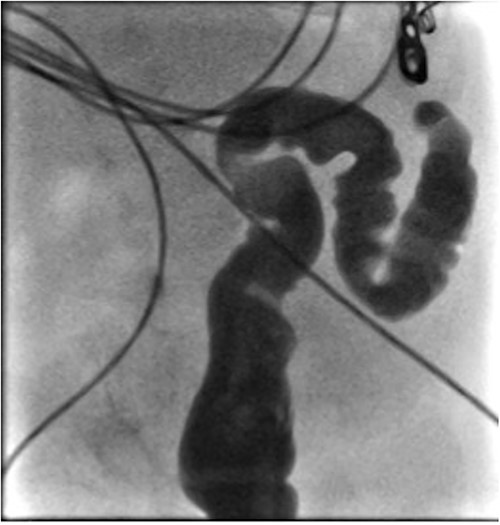

He presented at 6 weeks of age with circulatory shock requiring inotropic support and a short history of sudden abdominal distension and non bilious vomiting. He had been having regular episodes of SVT, all self limiting. Laparotomy demonstrated malrotation and a 540°midgut volvulus with extensive bowel necrosis. A fulcrum of ileum was densely adherent to the descending colon. Following intestinal resection he was left with 40 cm of small bowel from the duodenojejunal flexure, 2 cm of distal ileum and an intact colon. Following recovery from this acute episode he was managed for intestinal failure. A contrast enema was performed 10 days later in advance of stoma closure to examine the area of descending colon to which the ileum had been adherent at laparotomy. This demonstrated failure of passage of contrast proximal to the mid descending colon consistent with acquired colonic atresia (Fig. 1). Due to ongoing high stoma output and inability to progress enteral feeds, the infant proceeded to laparotomy, closure of jejunostomy, resection of colonic atresia, and anastomosis at 3 months of age. Macroscopic evidence of the atresia was encountered (Fig. 2). Histology reported a narrow calibre colon to either side of the atresia with fibrotic submucosa, focal fibrovascular proliferation, and clusters of giant cells. He subsequently achieved enteral autonomy.

Intra-operative photograph of acquired colonic atresia in descending colon consistent with radiological findings in Fig. 1.